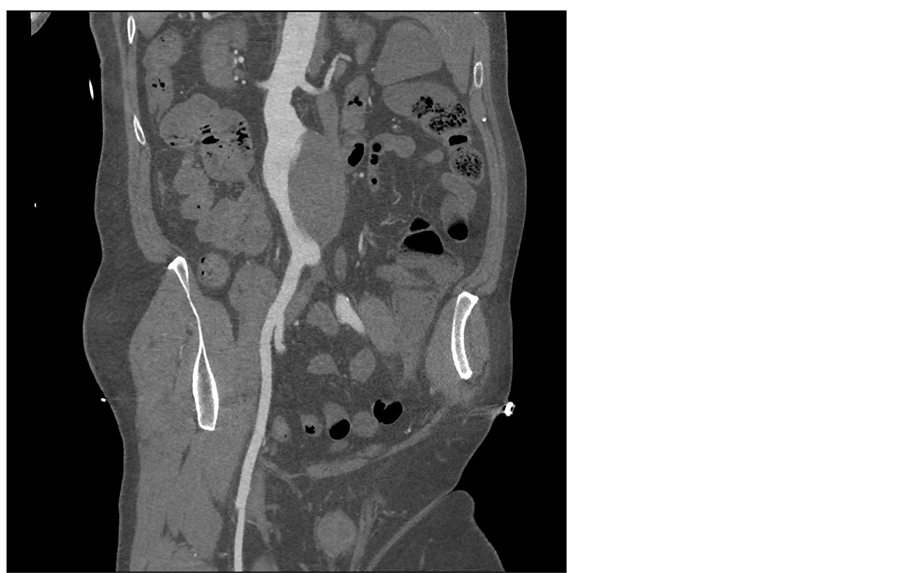

Lumbar medullar magnetic resonance imaging (MRI) was normal but showed an infrarenal AAA (Figure 1). The finding was subsequently confirmed by a contrast enhanced CT scan (Figure 2). The aneurysm was partially thrombosed with a maximal diameter of 7.5 cm with no signs for rupture.

Figure 2. Pre operative CT scan with curvilinear reconstruction showing an infra-renal aneurysm with lateral thrombosis.